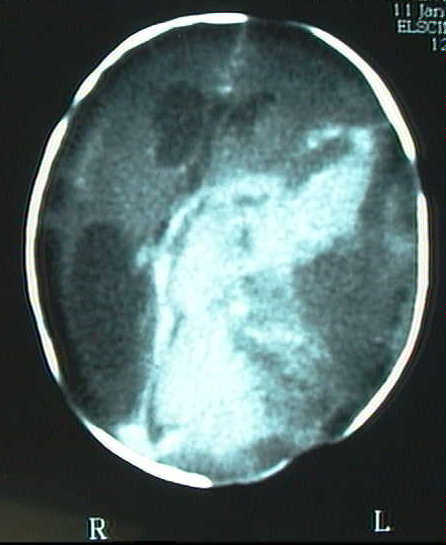

Figura 1 : Imagen por ecografía (a) y por Tomografía Computada con contraste (b). Se observa una gran masa tumoral ocupando la mayor parte del hemisferio izquierdo e hidrocefalia derecha.

En controles ecográficos y por tomografia computada posteriores (fig. 1a-b) se constata necrosis tumoral, dilatación de vena cava superior y shunt derecha-izquierda a nivel del ductus arteriosus; clínicamente se detecta proptosis izquierda, hipotensión, reborde hepático, e hiperbilirrubinemia que precisa fototerapia. Se practican estudios por Resonancia Magnética para estudio de extensión e intentar caracterizar la masa (fig 2a-c).